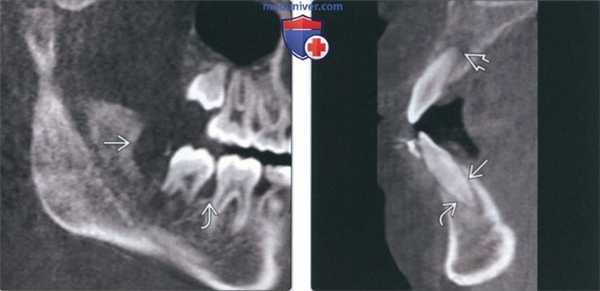

(Слева) На панорамной реформатированной КЛКТ у этого же пациента определяется окклюзионное смещение фолликула формирующегося зуба со слабо выраженной кортикальной пластинкой. Также определяется утрата костной ткани альвеолярного гребня, имитирующая заболевание периодонта.

(Справа) На КЛКТ (профильный срез) у этою же пациента определяется расширение пространства периодонтальной связки твердая пластинка выражена незначительно. Такие же изменения обнаруживаются при активном ортодонтическом лечении. Хлорома напоминает периапикальное воспалительное заболевание в области вершины резца верхней челюсти.